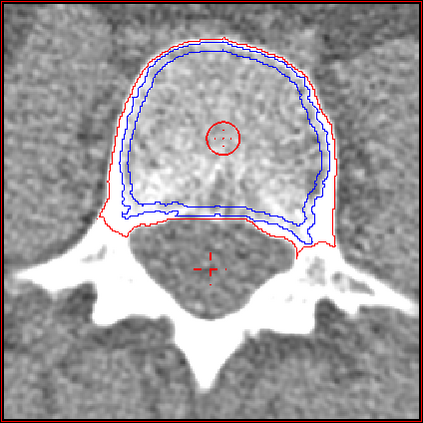

In this paper we present a new 3D segmentation approach for the vertebrae of the lower thoracic and the lumbar spine in spiral computed tomography datasets. We implemented a multi-step procedure. Its main components are deformable models, volume growing, and morphological operations. The performance analysis that included an evaluation of accuracy using the European Spine Phantom, and of intra-operator precision using clinical CT datasets from 10 patients highlight the potential for clinical use. The intra-operator precision of the segmentation procedure was better than 1% for Bone Mineral Density (BMD) and better than 1.8% for volume. The long-term goal of this work is to enable better fracture prediction and improved patient monitoring in the field of osteoporosis. A true 3D segmentation also enables an accurate measurement of geometrical parameters that can augment the classical measurement of BMD.